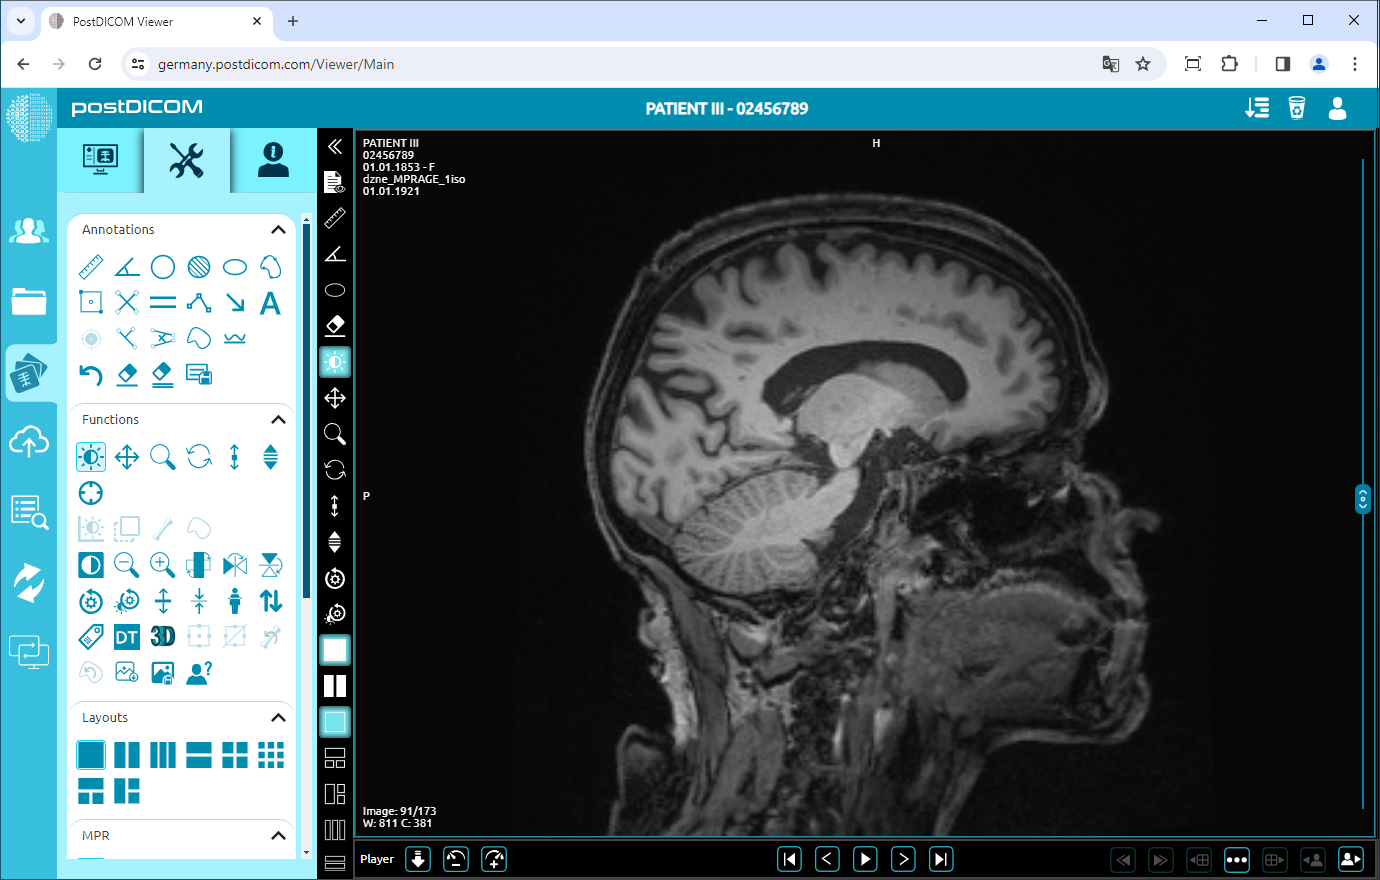

Flip Horizontal

To flip the image horizontally, click on the “Flip Horizontal” icon on the left side of the page.

After clicking, the horizontal mirror view of your image will be displayed on the viewport.